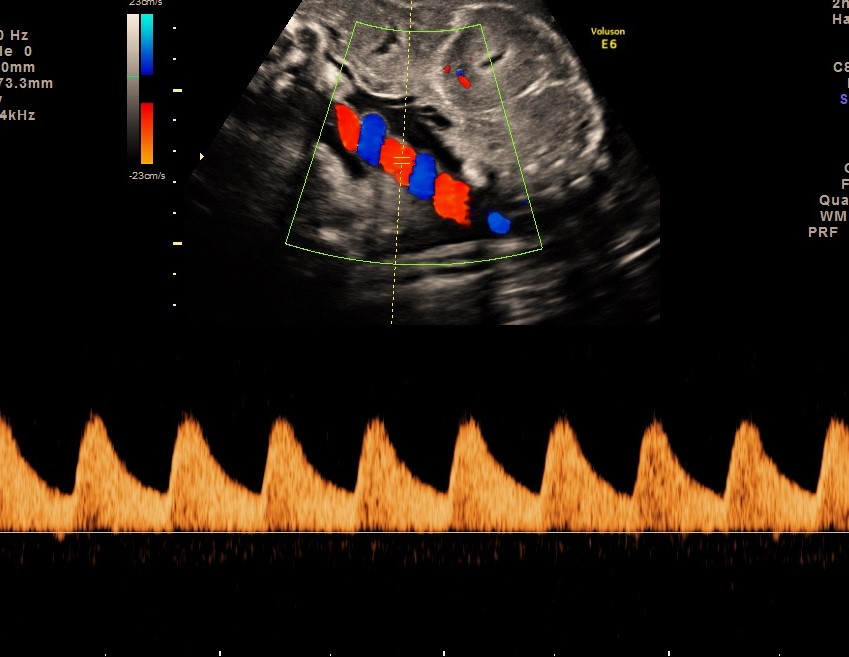

Doppler ultrasound is a specialised technique used to assess blood flow in key fetal and placental blood vessels. During growth scans, Doppler assessment helps evaluate placental function and how baby is adapting to the pregnancy. Commonly assessed vessels include:

• Umbilical artery, reflecting resistance to blood flow across the placenta

• Middle cerebral artery (brain), which can indicate fetal adaptation to reduced oxygen supply

• Ductus venosus (near the heart), assessed in selected cases to reflect fetal heart function

Doppler findings are particularly valuable in the third trimester and may influence monitoring strategies and timing of delivery.